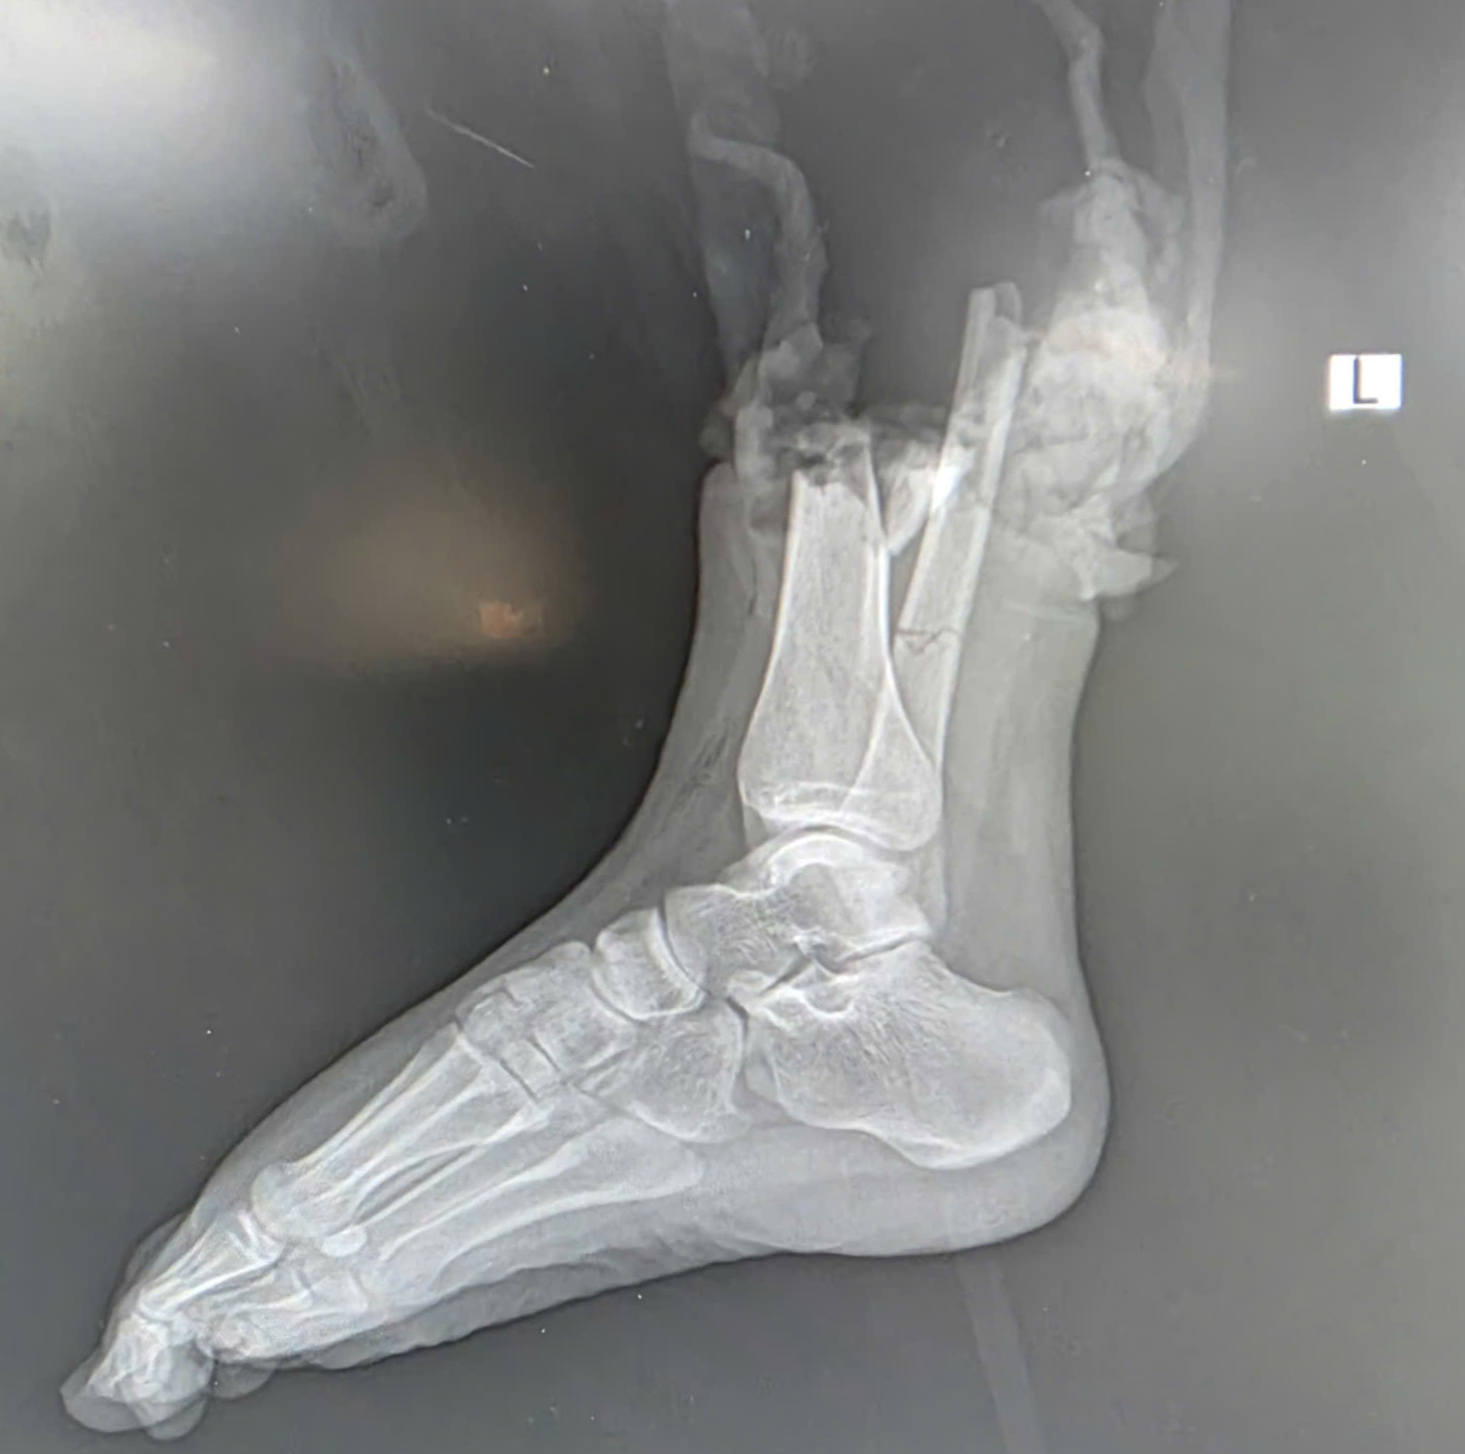

Hình ảnh chân của nạn nhân bị đứt rời sau tai nạn

Nạn nhân là chị Đ.P. (19 tuổi, ở Bắc Ninh), được phẫu thuật cấp cứu tại Khoa Chấn thương Chi trên và Vi phẫu thuật, Viện Chấn thương Chỉnh hình (Bệnh viện Trung ương Quân đội 108), trong tình trạng đứt lìa phức tạp ở 1/3 dưới cẳng chân phải, kèm dập nát phần mềm.